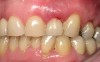

Figure 2  Clinical photograph of an implant restoration replacing the congenitally missing maxillary left lateral incisor. Note the cyanotic color changes, due to inflammation and cement, of the marginal gingiva in a 31-year-old female patient with thin biotype.

Figure 2